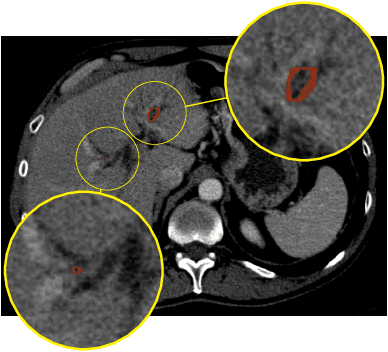

Abstract:Automatic liver lesion segmentation is a challenging task while having a significant impact on assisting medical professionals in the designing of effective treatment and planning proper care. In this paper we propose a cascaded system that combines both 2D and 3D convolutional neural networks to effectively segment hepatic lesions. Our 2D network operates on a slice by slice basis to segment the liver and larger tumors, while we use a 3D network to detect small lesions that are often missed in a 2D segmentation design. We employ this algorithm on the LiTS challenge obtaining a Dice score per case of 68.1%, which performs the best among all non pre-trained models and the second best among published methods. We also perform two-fold cross-validation to reveal the over- and under-segmentation issues in the LiTS annotations.